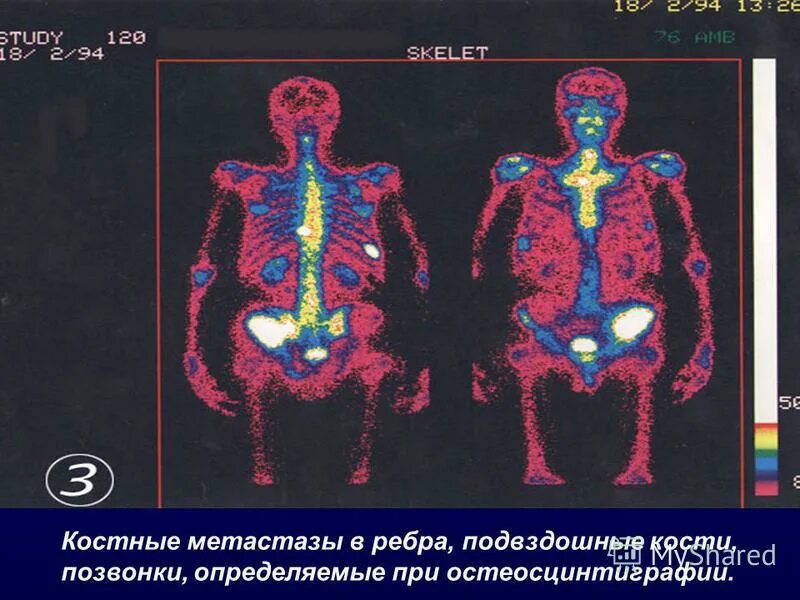

Метастазы в простате